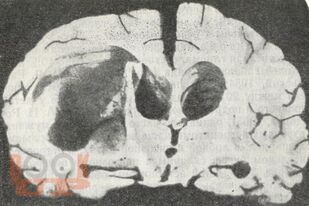

В представленном учебном пособии в виде краткого реферата во введении описано место опухолей головного мозга среди заболеваний у детей, их частота и локализация. Подробно описываются структурно-биологические свойства опухолей головного мозга (астроцитомы, глиобластомы, олигоденд-роглиомы, эпендимомы, менингиомы, краниофарингиомы, сосудистые опухоли, саркомы). Достаточно полно представлены клиника и диагностика опухолей мозга у детей, их особенности в зависимости от пола и возраста ребенка. В кратком заключении описываются затронутые вопросы. Весьма ценными являются вопросы для самоконтроля и тестовые задания. В указателе литературы даны основные источники, в том числе монографии самих авторов.